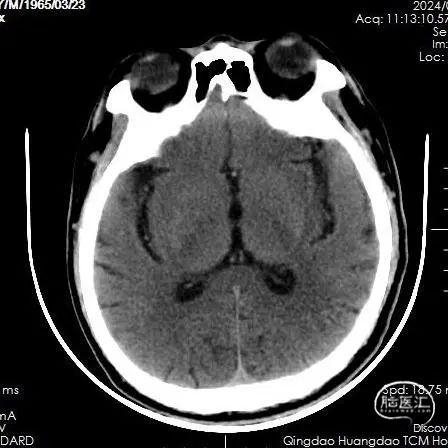

CT平扫:未见急性脑梗死早期病灶显影,未见大脑中动脉高密度征。

术后即刻复查脑CT,未见出血及梗死病灶。

后续完善磁共振检查:DWI示左侧皮层少许点状高信号,MRA示大脑中动脉分支显影良好。